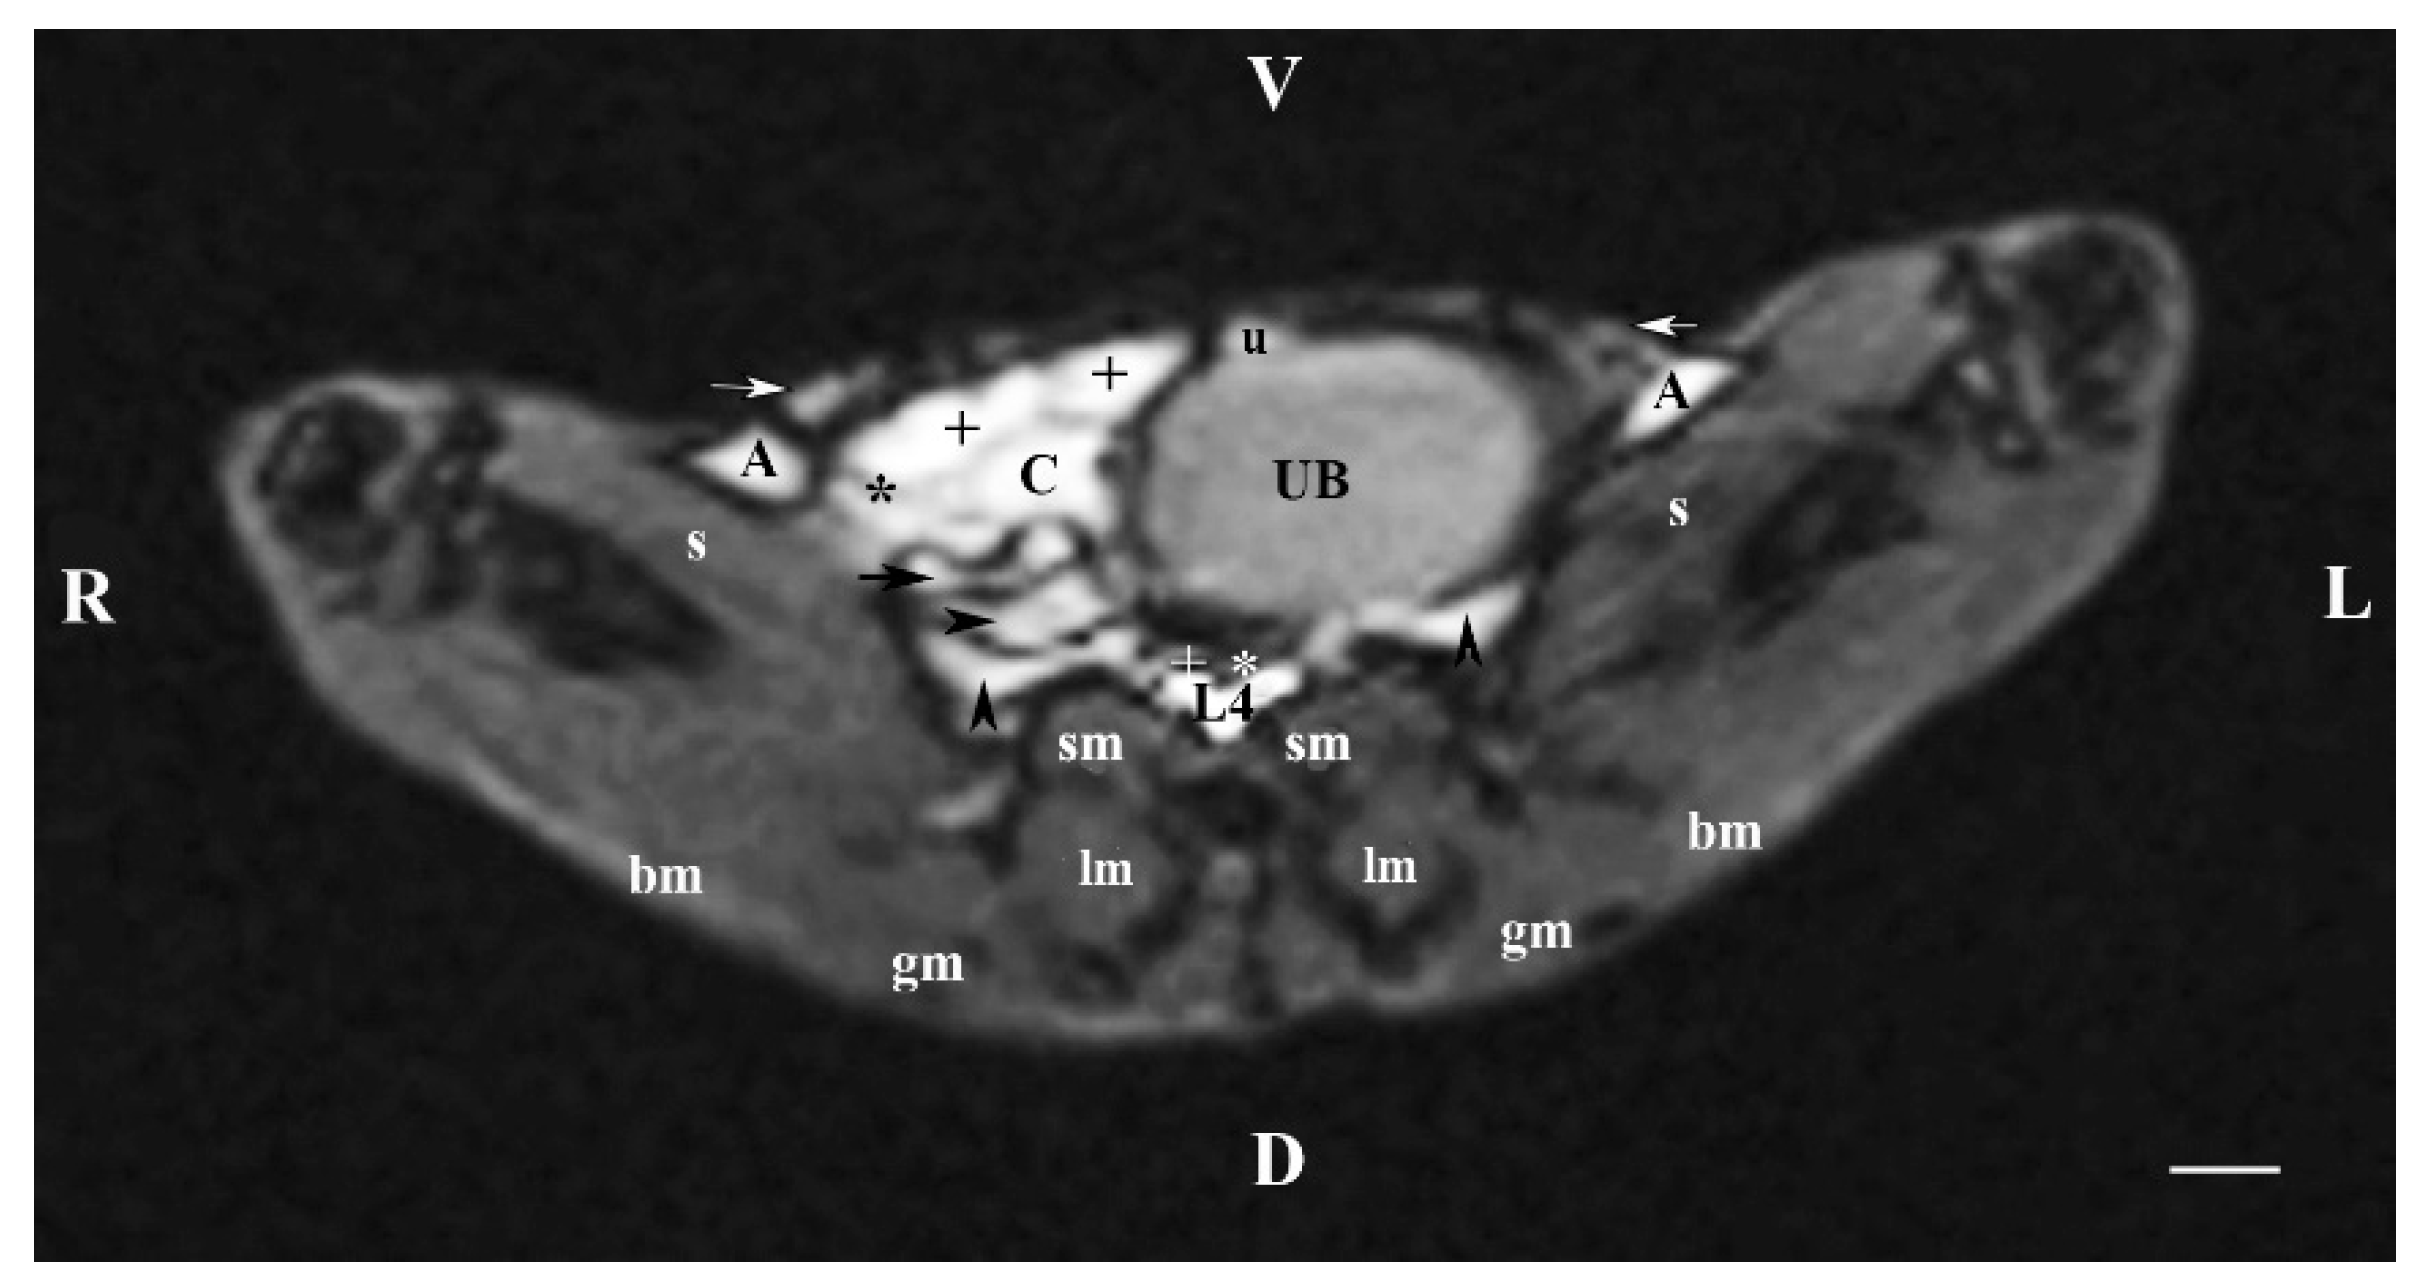

3.1. Transverse MRI